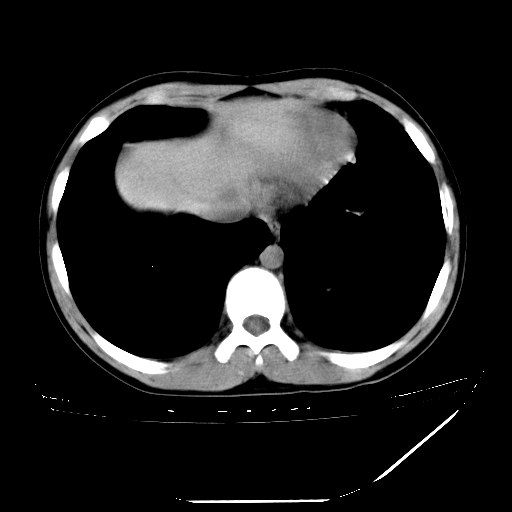

男,13岁,咳嗽、咳痰伴发热一周。

纵隔多发肿大淋巴结,部份有融合改变。双肺血管气管束增厚,以肺门为中心向外周散发,以左肺下叶为明显。考虑淋巴瘤可能性大。不除外原发综合征。

左肺野见淡片状影,病因整体多考虑结核

单纯看片子感觉左侧肺通气不畅,而不像肺内病变引起的纵隔病变。而且纵隔及左肺门都有淋巴结增大。首先还是考虑一下结节病,不排除淋巴瘤!!!